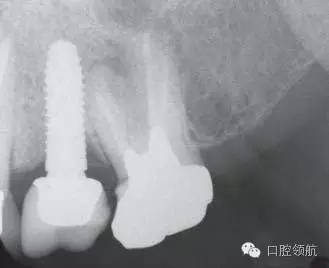

口內(nèi)檢查可見上部修復(fù)體有微動,沒有發(fā)現(xiàn)周圍黏膜組織的異常(圖1)。 X線影像可以看到種植體的周圍有一定程度的骨吸收但未發(fā)現(xiàn)周圍軟組織的異常(圖2)??紤]是基臺松動的可能性較高。向患者說明松動的原因,需要去除上部修復(fù)體后再度擰緊固定基臺螺絲。因上部修復(fù)體的固定使用的是臨時粘接劑。先嘗試使用去冠器,但未能去除。

圖2 X線攝影像上可以看到種植體的周圍有一定程度的骨吸收但未發(fā)現(xiàn)有周圍軟組織的異常(圖2)??紤]基臺松動的可能性較高。